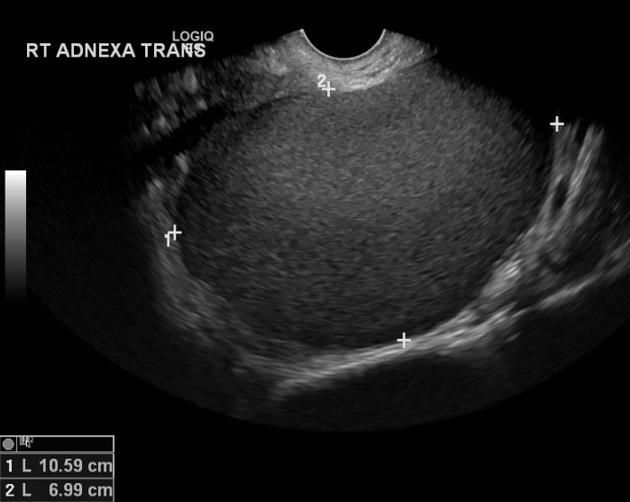

USG: endometrioma // RNM: nódulos

Localização mais comum: ovariana (endometrioma)

Endometrioma (cisto de chocolate)